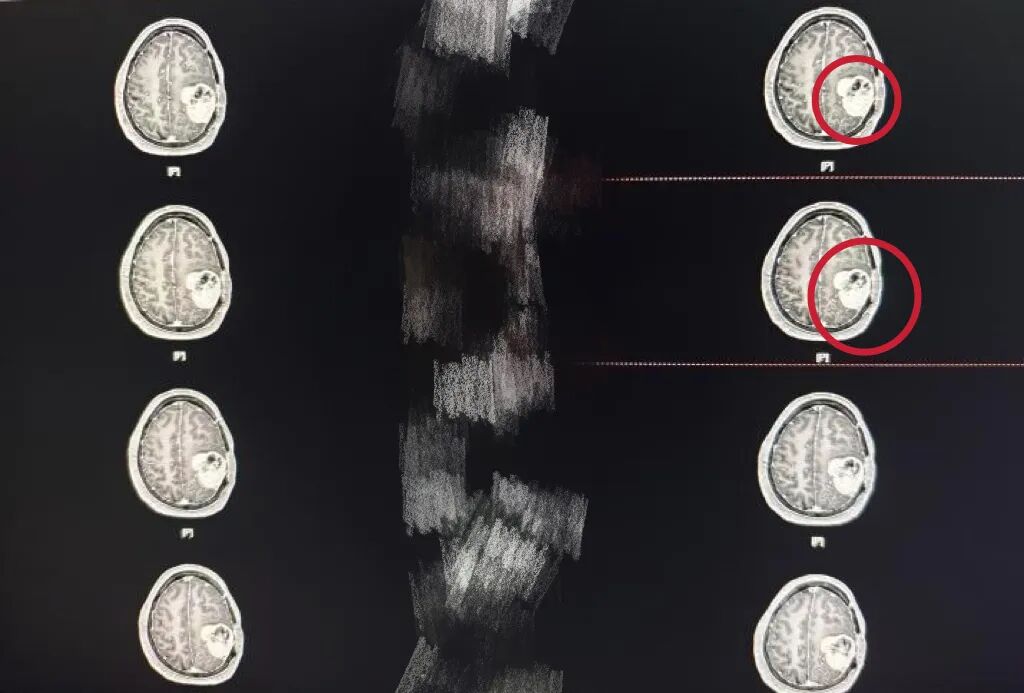

家住宿州的张大爷(化名)前段时间突然出现头部剧烈疼痛,恶心呕吐等症状,家人发现后急忙将其送往当地医院就诊,头颅MRI检查显示张大爷颅内存在多发性占位性病变,其中左侧顶叶肿瘤体积巨大,已严重压迫周围脑组织,导致脑功能受损。当地医院建议尽快手术,但患者既往有多次脑肿瘤手术史,左侧头皮因反复手术变得薄弱如纸,且合并冠心病、高血压等基础疾病,手术风险极高。

神经外科三病区陆路副主任医师了解清楚张大爷的病情后,迅速组织神经外科、麻醉科、重症医学科等多学科专家会诊。陆主任表示:“患者的情况远超预期:左侧头皮因多次手术形成瘢痕,血供极差,切口愈合风险高;颅内肿瘤与重要神经血管紧密粘连,稍有不慎即可能引发偏瘫、失语等严重并发症;基础疾病导致心肺功能脆弱,麻醉耐受性极差。”

经过反复推演,陆主任以及神经外科医护团队制定了“瘤内减压+分步切除”的手术策略,并依托高清神经导航系统、术中超声及显微镜等设备,规划出一条避开功能区的“安全路径”。

术中,陆主任在高清神经导航引导下,首先通过瘤内减压技术逐步释放肿瘤内部压力,避免因突然减压引发脑组织移位。随后,借助显微镜的超高放大倍数,再逐步分离肿瘤与正常脑组织的粘连界面,精准避开运动区、语言区等关键功能区。

“左侧顶叶肿瘤体积大、血供丰富,稍有不慎就会损伤脑功能。”陆主任说道:“我们像拆解‘定时炸弹’一样,先切断肿瘤的‘营养线’,再分块移除,最终完整切除了肿瘤及受侵犯的硬脑膜。最大程度的保护正常脑组织功能。”